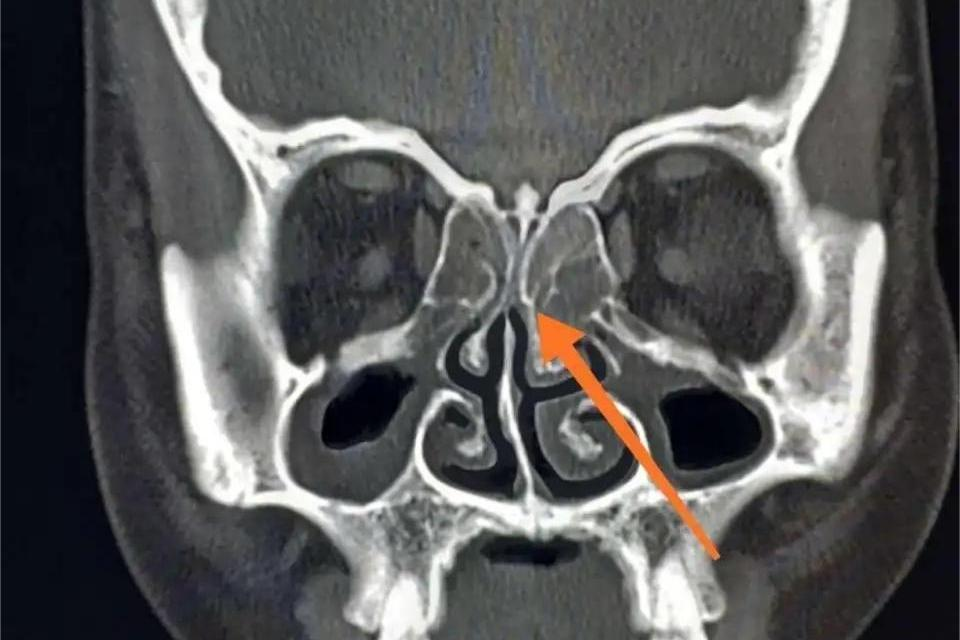

右侧上颌窦黏膜增厚是在影像学检查中常见的一种表现,指的是右侧上颌窦内的黏膜层厚度增加,可能由鼻炎、过敏反应、鼻腔结构异常变等引起,需根据病因采取治疗。

3、鼻腔结构异常:

- 鼻中隔偏曲、鼻甲肥大、鼻息肉等鼻腔结构异常,可影响鼻腔和鼻窦的通气引流,导致窦腔内长期处于低氧、高负压状态,刺激黏膜增生、肥厚,应进行鼻中隔矫正术、鼻甲部分切除术、射频消融术等方式进行治疗。